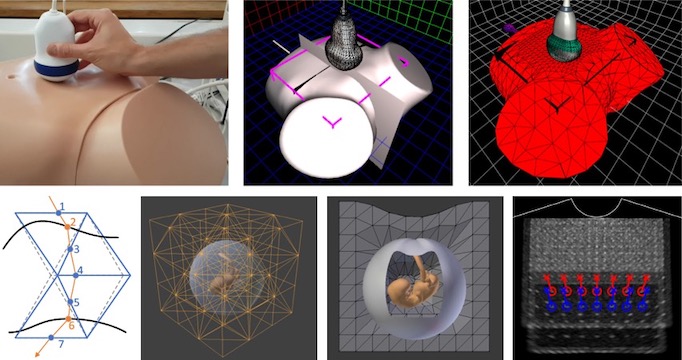

[2019] Rastislav Starkov, Lin Zhang, Michael Bajka, Christine Tanner, and Orcun Goksel:

"Ultrasound Simulation with Deformable and Patient-Specific Scatterer Maps",

Int J Computer Assisted Radiology and Surgery 14(9):1589-1599, Aug 2019.

[2019] Rastislav Starkov, Lin Zhang, Michael Bajka, Christine Tanner, and Orcun Goksel:

"Ultrasound Simulation with Deformable and Patient-Specific Scatterer Maps",

Int J Computer Assisted Radiology and Surgery 14(9):1589-1599, Aug 2019.

[2019] Rastislav Starkov, Christine Tanner, Michael Bajka, and Orcun Goksel:

"Ultrasound Simulation with Animated Anatomical Models and On-the-Fly Fusion with Real Images via Path Tracing",

Computers & Graphics 82:44-52, May 2019.

[2019] Rastislav Starkov, Christine Tanner, Michael Bajka, and Orcun Goksel:

"Ultrasound Simulation with Animated Anatomical Models and On-the-Fly Fusion with Real Images via Path Tracing",

Computers & Graphics 82:44-52, May 2019.

[2021] Lin Zhang, Tiziano Portenier, and Orcun Goksel:

"Learning Ultrasound Rendering from Cross-Sectional Model Slices for Simulated Training",

International Journal of Computer Assisted Radiology and Surgery 16:721-730, Apr 2021.

[2021] Lin Zhang, Tiziano Portenier, and Orcun Goksel:

"Learning Ultrasound Rendering from Cross-Sectional Model Slices for Simulated Training",

International Journal of Computer Assisted Radiology and Surgery 16:721-730, Apr 2021.